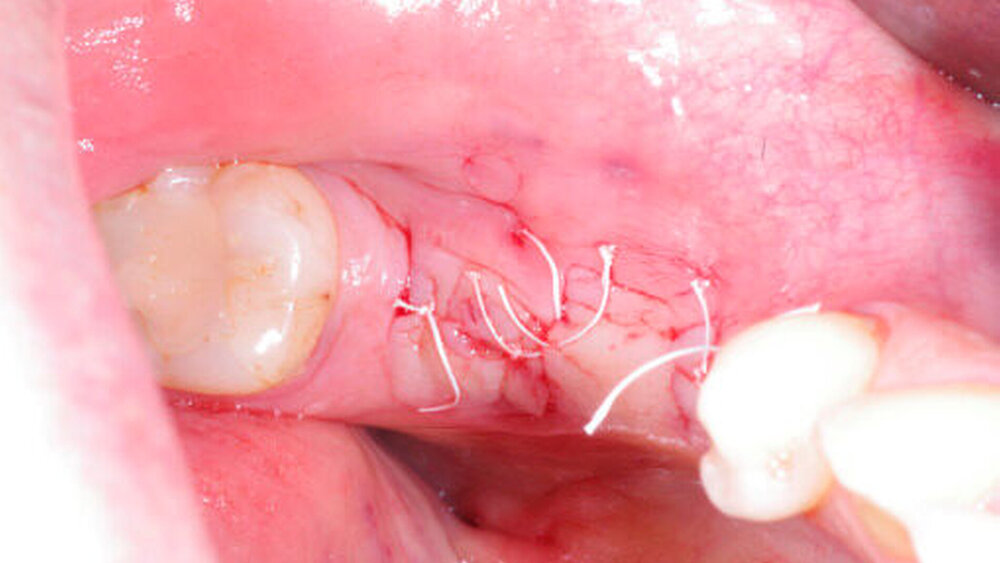

Die innovative Kombination aus weißem Faden und schwarzer Nadel ermöglicht exzellente Sichtbarkeit im OP-Gebiet. DirectFlon ist ein monofiles Nahtmaterial. Die glatte Oberfläche verhindert die Akkumulation von Bakterien und Essensresten. Im Gegensatz zu anderen Nahtmaterialien verhindern die Enden des PTFE-Fadens Irritationen an den Schleimhäuten.

Last but not least: Aufgrund seiner geringen Kapillarwirkung kann der Faden außerdem einfach entfernt werden. Das beeinflusst die Wundheilung positiv und verringert die Schwellung für den Patienten.